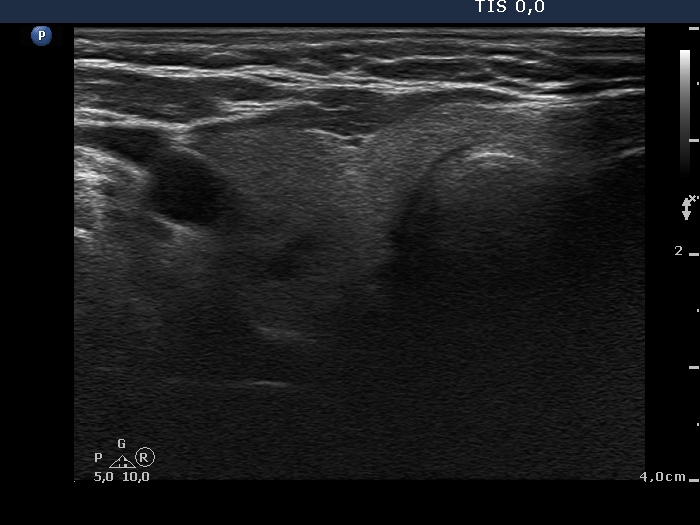

Ultrasonography. There were two nodules in the left lobe. The upper one was echonormal while the lower hypoechogenic one contained microcalcification and a cotton-like larger hyperechogenic patch and presented an irregular shape and an intranodular vascularity.